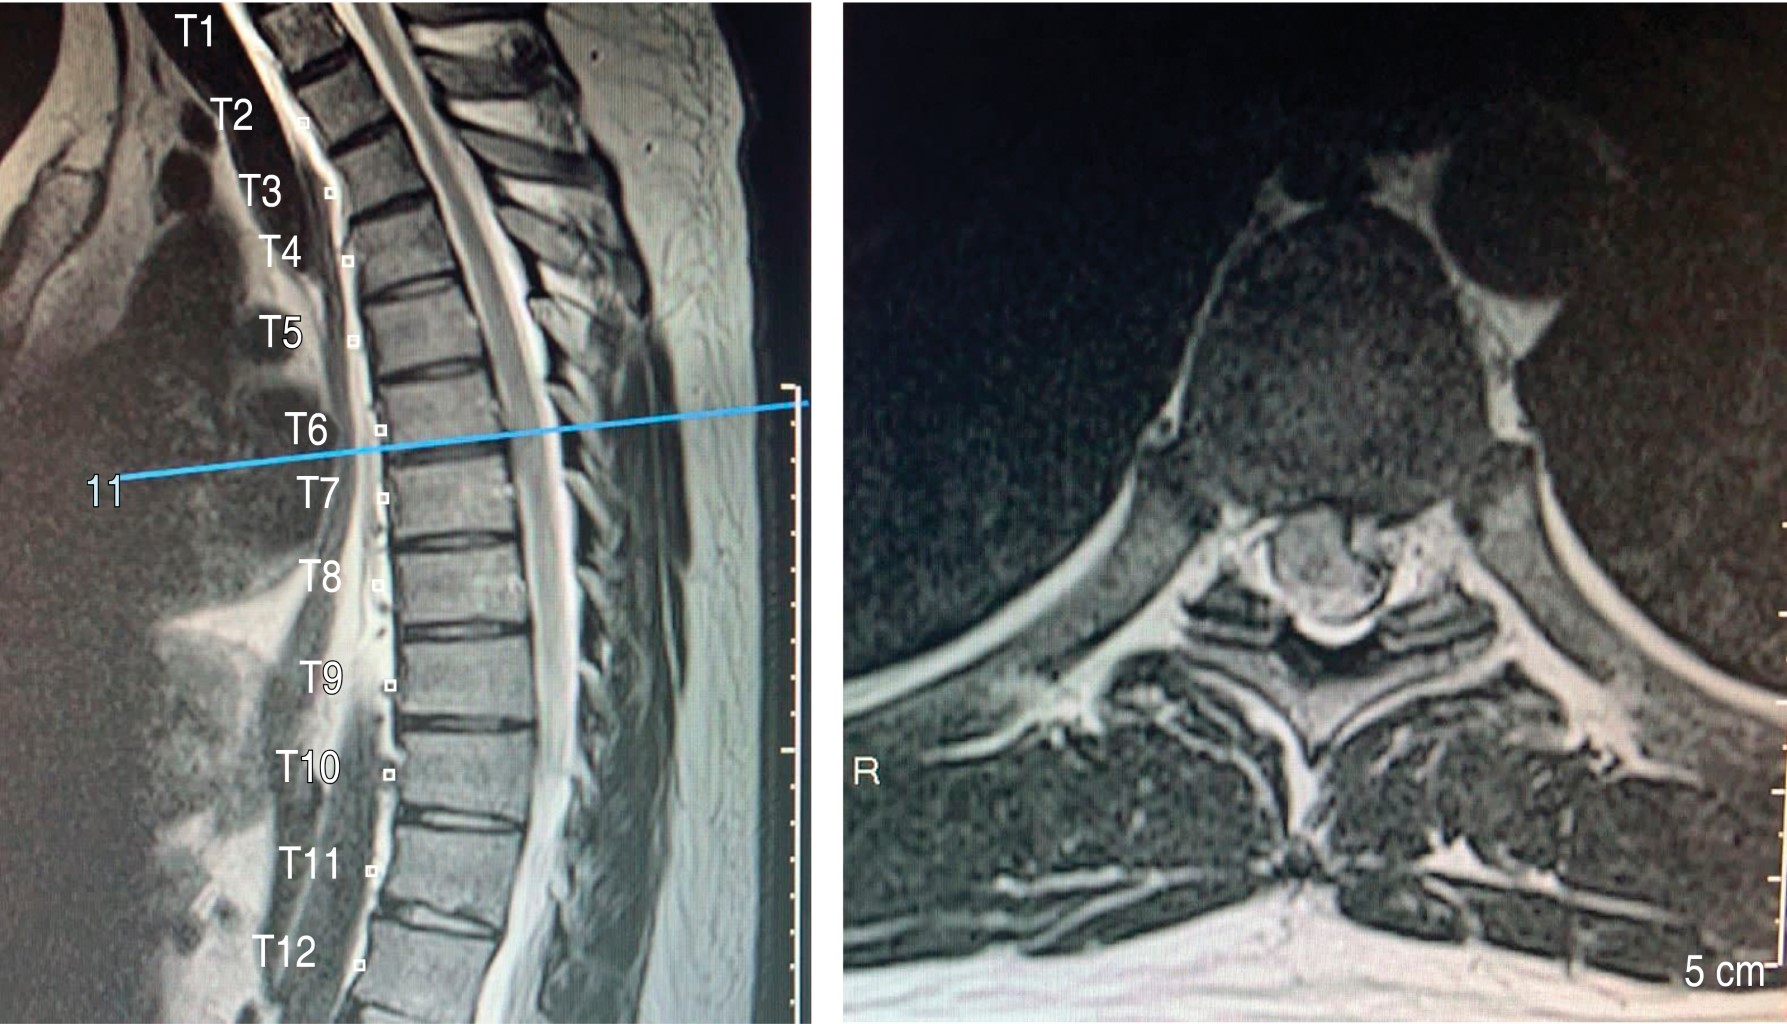

Se realizan estudios de imagen, radiografías y tomografía axial computarizada sin alteraciones, la resonancia magnética simple de columna cervical y torácica con neuroeje en T2 revela hernia discal paracentral izquierda T6-T7, la cual genera compresión medular (Figuras 1 y 2).

Figura 1

Figura 2